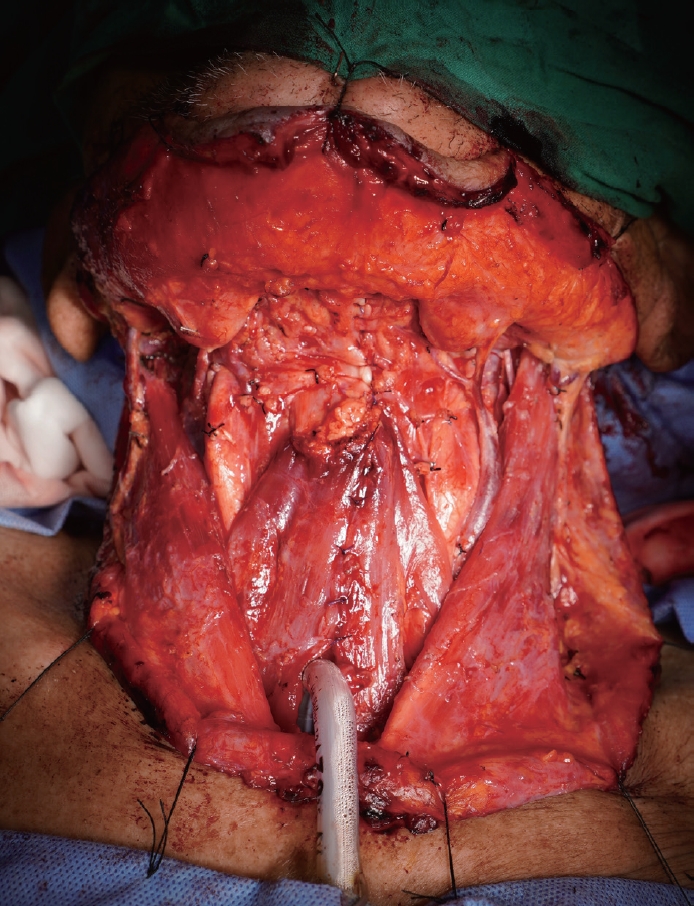

Fig. 4.

The anterior defect of oropharyngeal and hypopharyngeal wall is developed with total laryngectomy.

kjorl-hns-2022-00416f4.jpg

Fig. 5.

The pharynx is closed primarily.

kjorl-hns-2022-00416f5.jpg

Fig. 6.

The bilateral muscle flaps are anchored at the inferior 2/3 of the anterior surface of the pharyngeal closure and approximated at the middle.